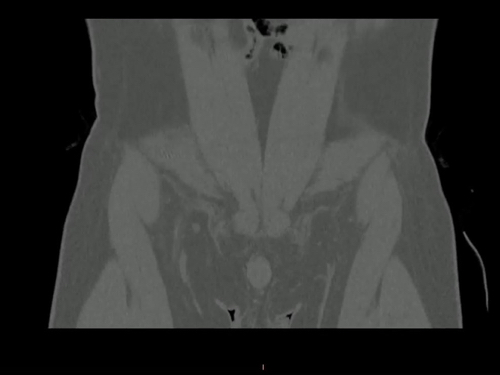

病例【骨肌】左侧髂骨占位?腰部外伤后腰痛5小时,男,39岁。

【患者信息】:男,39岁。

【主诉】:腰部外伤后腰痛5小时。

【现病史及既往史】:无手术史。

【检查】